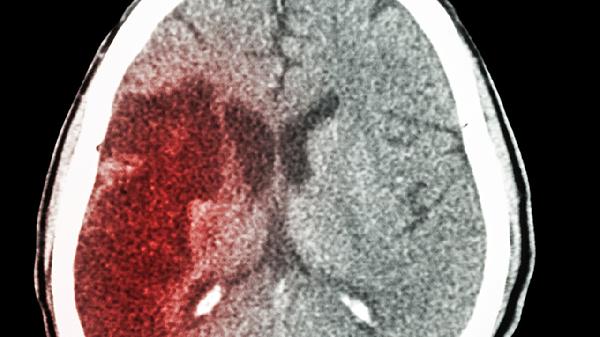

治疗脑供血不足的药物主要有阿司匹林肠溶片、尼莫地平片、盐酸氟桂利嗪胶囊、银杏叶提取物片、长春西汀片等。脑供血不足可能与动脉粥样硬化、颈椎病、高血压等因素有关,通常表现为头晕、头痛、视物模糊等症状。建议及时就医,在医生指导下规范用药。